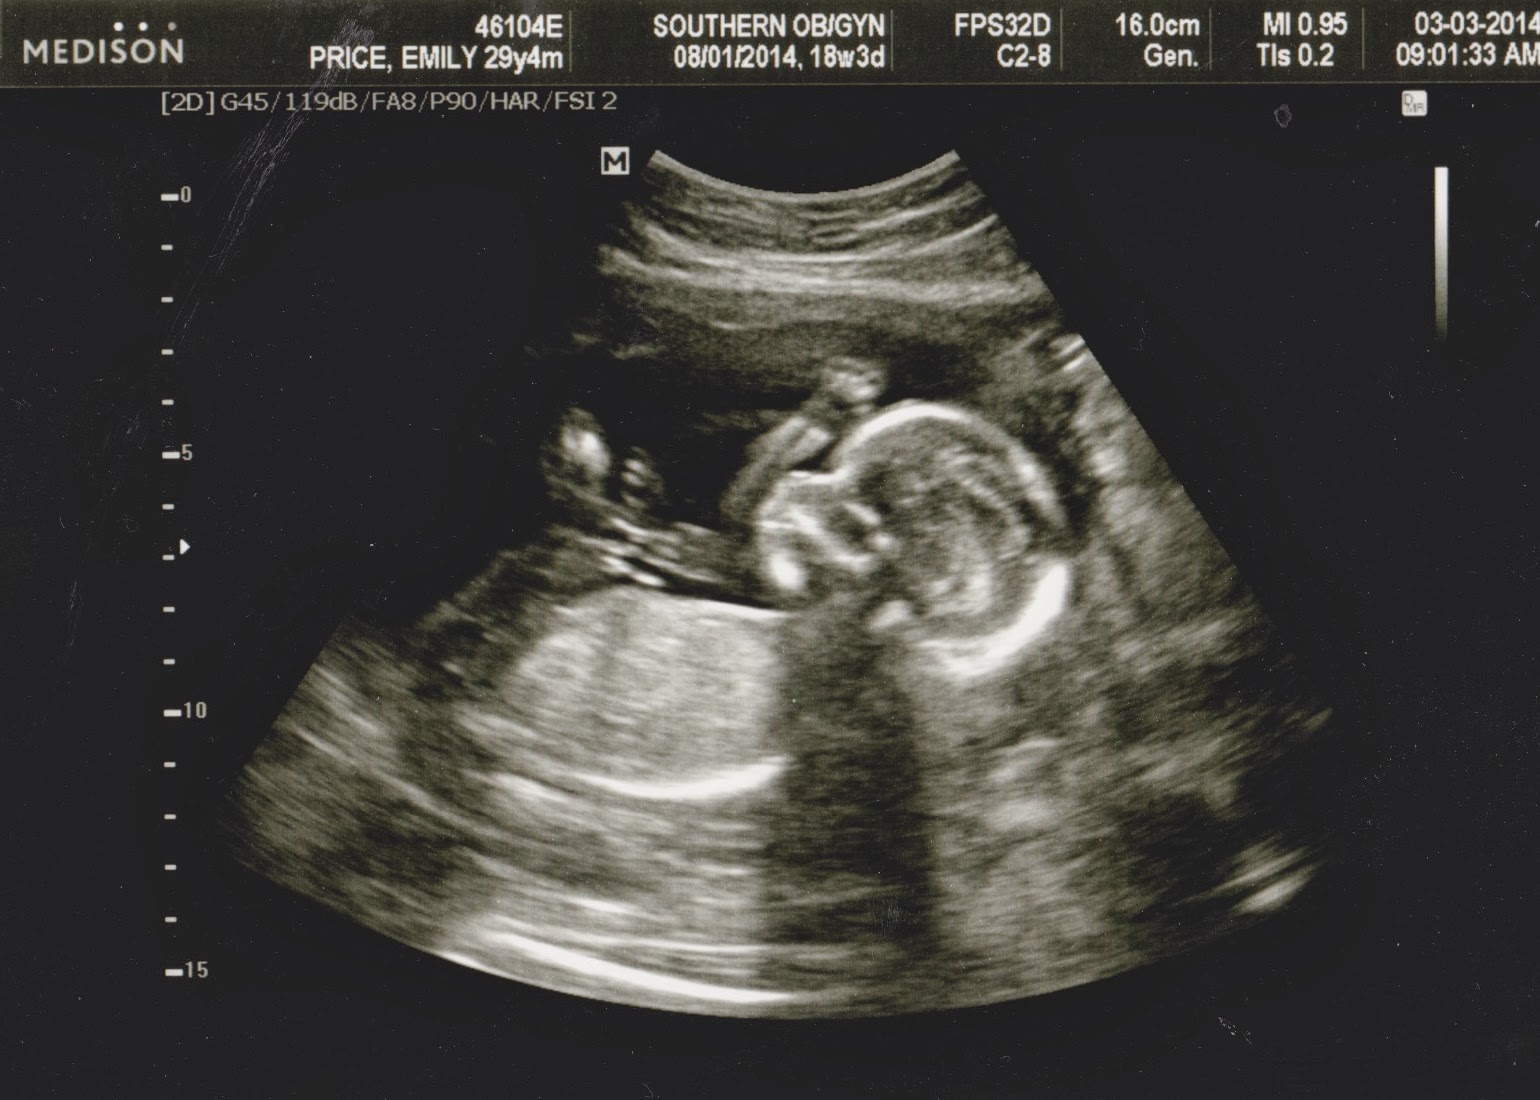

From www.journeyofparenthood.com

The Journey of Parenthood... 18 Week OBGYN Visit and Ultrasound! What Does Yellow Mean On Ultrasound ultrasounds are valuable in healthcare to visualize internal organs and tissues. Red color indicates blood flow towards the transducer or probe. yellow or orange color. This allows you to assess flow velocities on the. what do yellow or orange mean on an ultrasound? power doppler is an ultrasound modality, which uses only the amplitude of the. What Does Yellow Mean On Ultrasound.